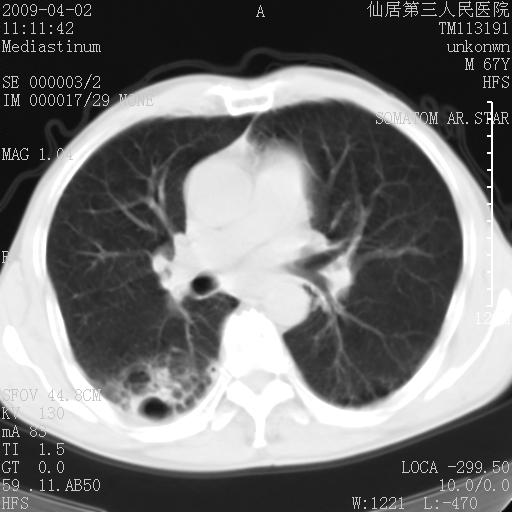

患者老年男性,乏力畏寒来诊,摄胸片示右下肺感染性病变,抗炎两周后复查胸片,无好转有进展。

后做ct平扫表现如下:

考虑右肺炎症可能性大,不除外细支气管肺泡癌

是否还要考虑肺间质纤维化,建议hrct扫描。

病灶呈蜂窝征,纵隔多个淋巴结肿大;肺泡癌需考虑

右肺下叶背段干酪性肺炎。请痰检[emb28]

我认为普通的感染应该可以除外,间质性肺炎可能性较大,但如何解释纵膈的淋巴结肿大呢

考虑双肺间质性改变(间质纤维化?)伴右肺下叶感染。